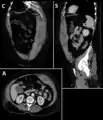

A rectus sheath hematoma is an accumulation of blood in the sheath of the rectus abdominis muscle. It causes abdominal pain with or without a mass.

The hematoma may be caused by either rupture of the epigastric artery or by a muscular tear. Several factors have been identified as predisposing risks for rectus sheath hematoma, including coughing, straining, exercise, hypertension, obesity, previous abdominal surgery, subcutaneous injection, trauma and anticoagulant therapy. With an ageing population and the widespread use of anticoagulant medications, there is evidence that this historically benign condition is becoming more common and more serious.[1] Anticoagulant therapy is used to treat many diseases. However, in the COVID-19 pandemic, anticoagulant therapy was frequently used and therefore the incidence of rectus sheath hematoma increased.[2][3] Given that thrombotic events have been documented in numerous studies, it is advisable to initiate prophylactic and anticoagulant treatment during the early phase of COVID-19 disease. [4]